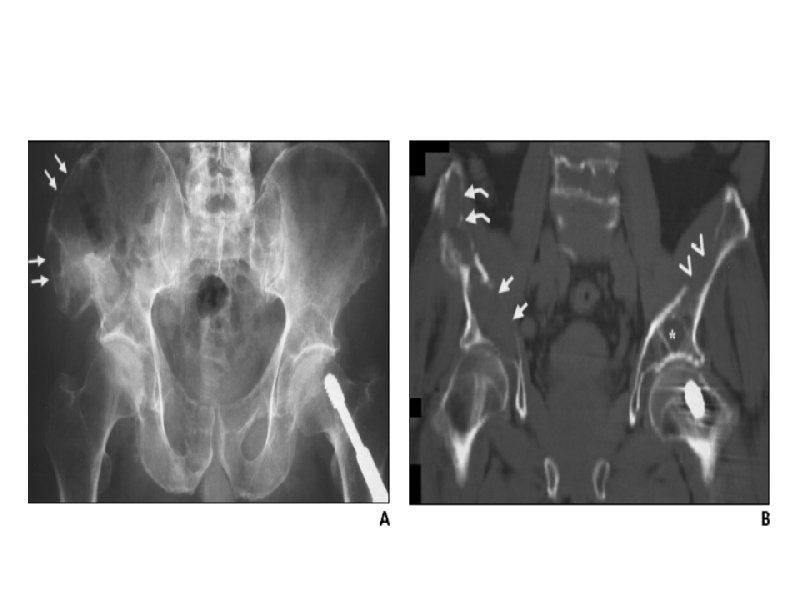

Лимфомы

Неходжкинские лимфомы низкой степени злокачественности